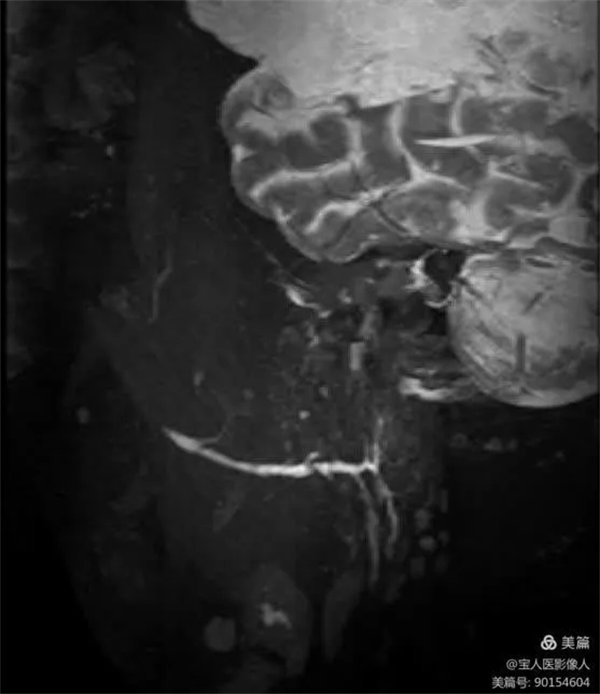

患者磁共振檢查,可清晰地顯示正常腮腺導管主干和大分支導管。

圖1,右側腮腺主導管和分支

醫學影像科副主任張軍暉醫生介紹,此圖像是在常規檢查中重建顯示腮腺導管主干及部分分支。如果行專門的腮腺導管磁共振成像技術,通過一些前期準備及掃描技術優化,成像效果會更好,結合強大的后處理技術,會更好的顯示腮腺導管及周圍組織結構。

2、腮腺導管MR成像,為無創性檢查,無需造影劑,避免了X線造影可能因造影劑產生的不良反應及導管破裂及感染的風險,更加安全,已逐步替代腮腺X線造影檢查。